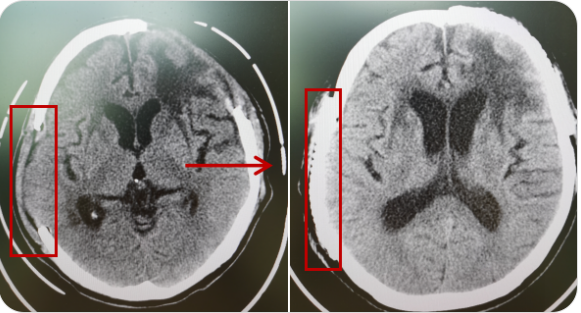

精通颅内动脉瘤介入栓塞和手术夹闭双技术,系统掌握脑动静脉畸形、颈内动脉海绵窦漏、硬脑膜动静脉漏等颅内血管疾病的诊疗和手术,精通颈动脉、椎动脉狭窄的血管内重建技术,以及颈动脉狭窄的内膜剥脱手术技术。在颅内肿瘤、椎管内肿瘤、颅脑损伤、高血压脑出血等疾病的诊治和手术,脑功能性疾病立体定向手术治疗等方面也积累了丰富的经验。

擅长脑血管病(出血与缺血)的神经介入与微创手术,能熟练开展脑外伤、重度颅脑损伤的救治工作。